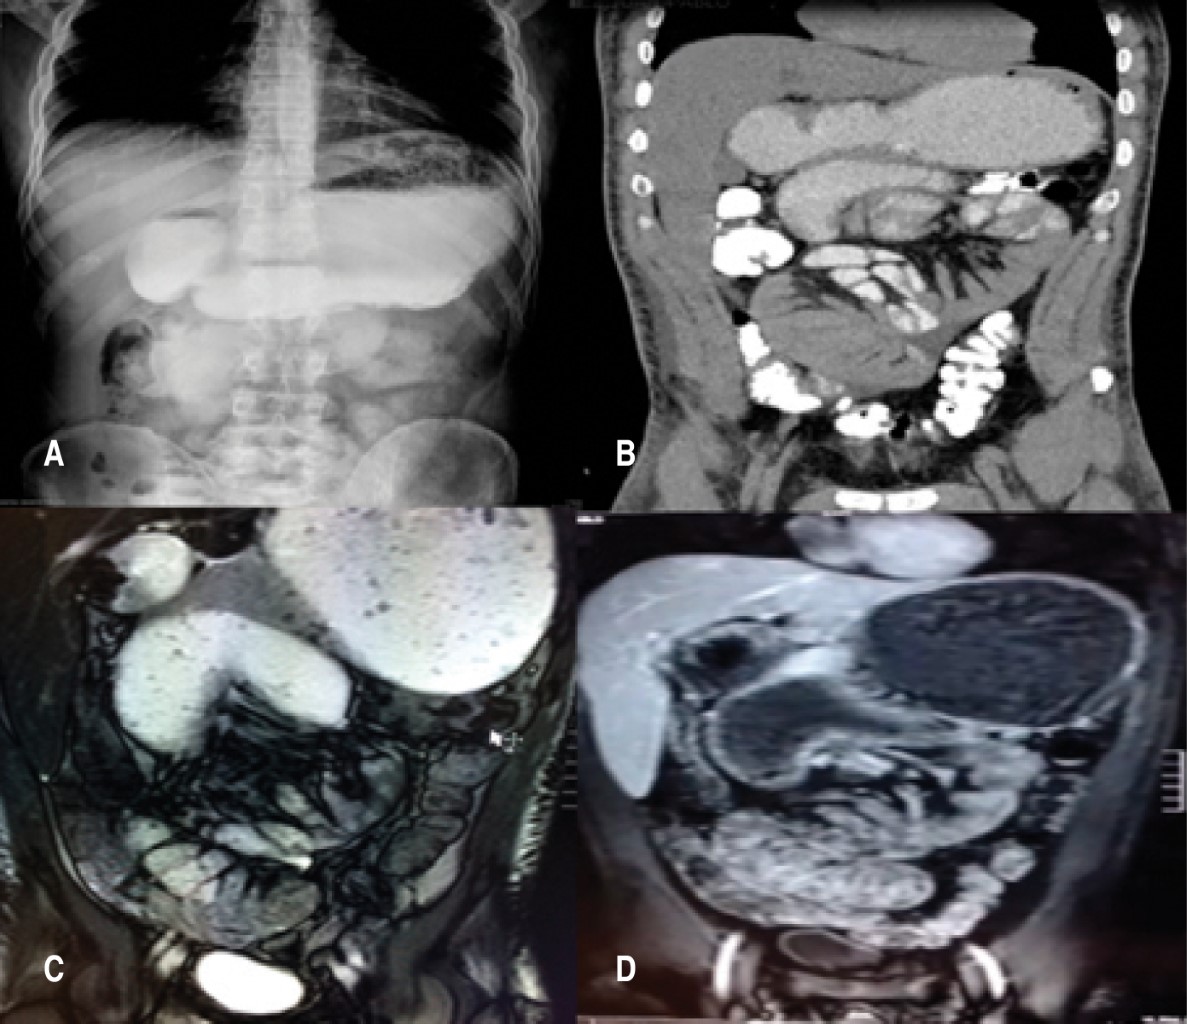

Se protocolizó con pruebas de laboratorio y reportó leucocitos 11.37 x 103/µl, hemoglobina 17.4 g/l, hematocrito 33.8%, glucosa 85 mg/dl, urea 35 mg/dl, creatinina 0.9 mg/dl, sodio 145 mmol/l, potasio 4.3 mmol/l. Sin otra alteración en resto de valores reportados. En la radiografía de abdomen se observó imágenes compatibles con asas de intestino delgado aumentadas de tamaño, niveles hidroaéreos de predominio en epigastrio y mesogastrio, sin datos de aire libre en cavidad. El tránsito intestinal con medio hidrosoluble y la tomografía contraste oral e intravenoso de abdomen, revelaron distensión de asas de intestino delgado a distintos niveles, presencia de gas en ámpula rectal, paso de medio de contraste por delante de arteria mesentérica, ángulo arterial mayor a 25o, se descartó síndrome de pinza mesentérica (síndrome de Wilkie). Se realizó enterorresonancia magnética en la cual se observan las cuatro porciones del duodeno distendidas y aumento de tamaño en yeyuno proximal. Endoscopia en la que se reportó esofagitis C de Los Ángeles, gastropatía crónica folicular, estómago retencionista, distensión en segunda y tercera porción duodenal y por delante de ellas. Con lo que se llegó al diagnóstico de obstrucción intestinal parcial (Figura 1).

Setenta por ciento de los casos de PCEE son diagnosticados de forma incidental durante una laparotomía cuando ésta se manifiesta en forma asintomática, el diagnóstico es difícil de concluirse antes de la cirugía porque los resultados de los análisis bioquímicos suelen ser normales y los hallazgos imagenológicos no suelen ser específicos. La radiografía simple de abdomen puede mostrar datos compatibles con síndrome de obstrucción intestinal como encontrar niveles hidroaéreos en asas intestinales y distensión de las mismas, o distribución anormal del patrón de aire en el tubo digestivo. En el caso que reportamos, en la tomografía abdominal con contraste oral e intravenoso se apreció un conglomerado de asas delgadas, rodeadas de una pared de tejido denso. Sin embargo, el diagnóstico preoperatorio del AC requiere un alto grado de sospecha clínica.14

El paciente del presente caso acudió sin antecedentes quirúrgicos o crónico degenerativos, además de sintomatología digestiva inespecífica. En el protocolo diagnóstico, el estudio endoscópico sugirió cuadro compatible con obstrucción por delante de la segunda porción duodenal; por lo que se continuó el estudio con tránsito intestinal y la tomografía abdominal contrastada, las cuales fueron de utilidad para descartar otras causas de obstrucción intestinal; se refiere de la TAC una sensibilidad y especificidad de hasta el 93%, aunque en el caso presentado sólo aportó datos de distensión poco habitual de asas del yeyuno proximal. La enterorresonancia muestra imagen típica de "coliflor"; sin embargo, no se incluyó en las posibilidades diagnósticas en el preoperatorio.

Figura 1